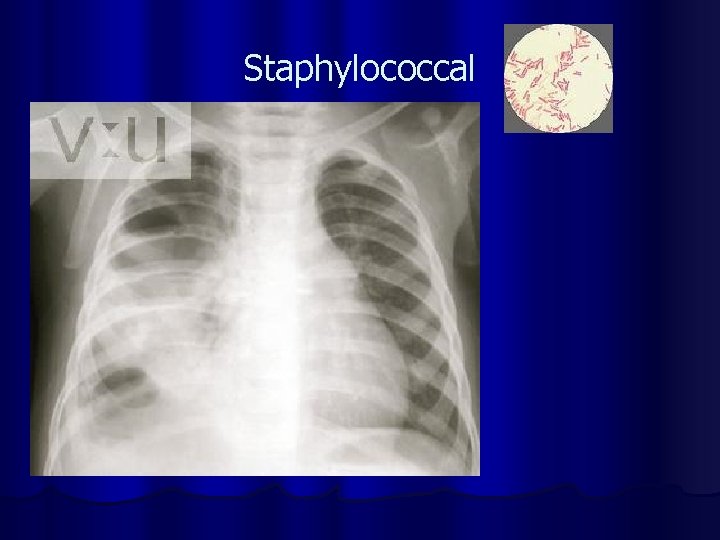

Hospital Acquired Pneumonia Two days after hospital admission l Etiology l Gram negative bacteria l Staphylococcal aureus l Anaerobic organisms l Lobar pneumonia causing organisms l

Staphylococcal